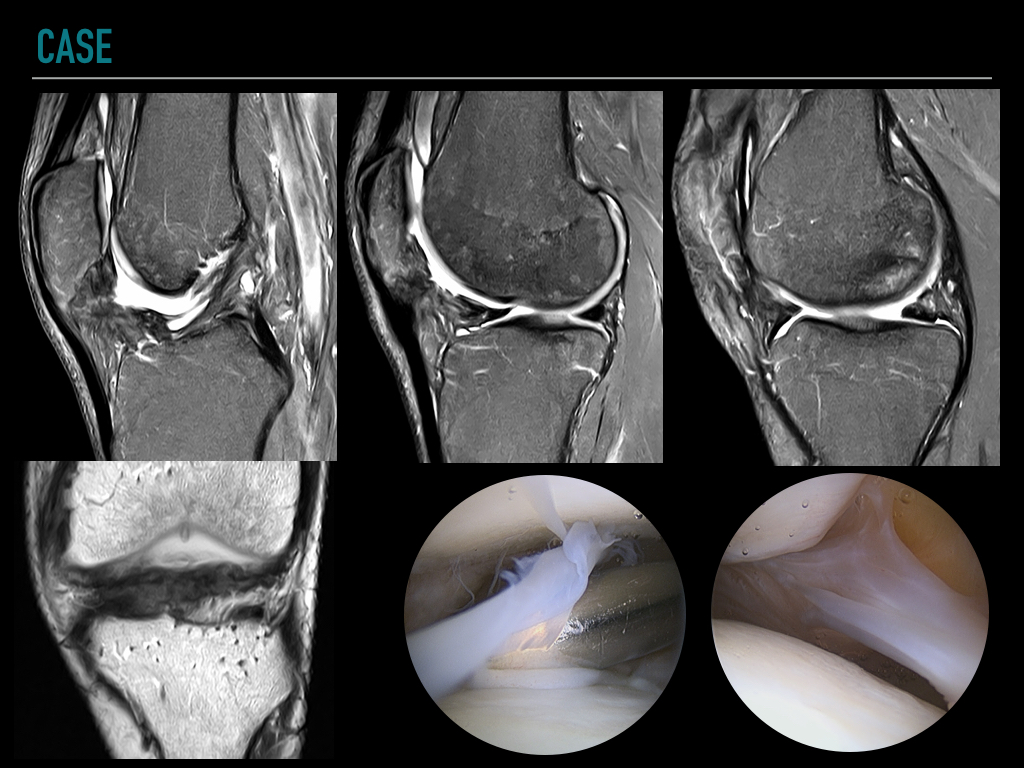

49-year-old man with limitation and painful flexo-extension after partial medial meniscectomy

At MR imaging, generalized arthrofibrosis is seen extending into the infrapatellar fat pad, suprapatellar recess and the posterior joint capsule. Thickening of the sinovial plicas and intraarticular fibrous bands are also common findings.

The treatment for knee arthrofibrosis includes physical therapy, and arthroscopic surgery. Reference article.